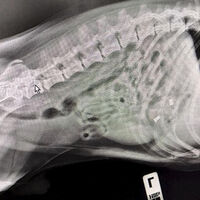

В пресс-службе ведомства уточнили, что владельцы привели к ветеринарам питомца по кличке Смайл с подозрением, что он съел игрушечного дракона. Терапевт Алексей Щукин и УЗ-диагност Елена Сухарева провели УЗИ и рентген. В ходе исследований стало понятно, что внутри собаки находится не один предмет.

«Поскольку Смайла доставили в ветклинику сразу же после происшествия, обошлось без операции. Специалисты вызвали медикаментозную рвоту и удалили предметы из желудка собаки», – отметили в пресс-службе.

Специалисты извлекли из Смайла кусок игрушки и итальянские серьги из муранского стекла. После этого его отпустили домой.